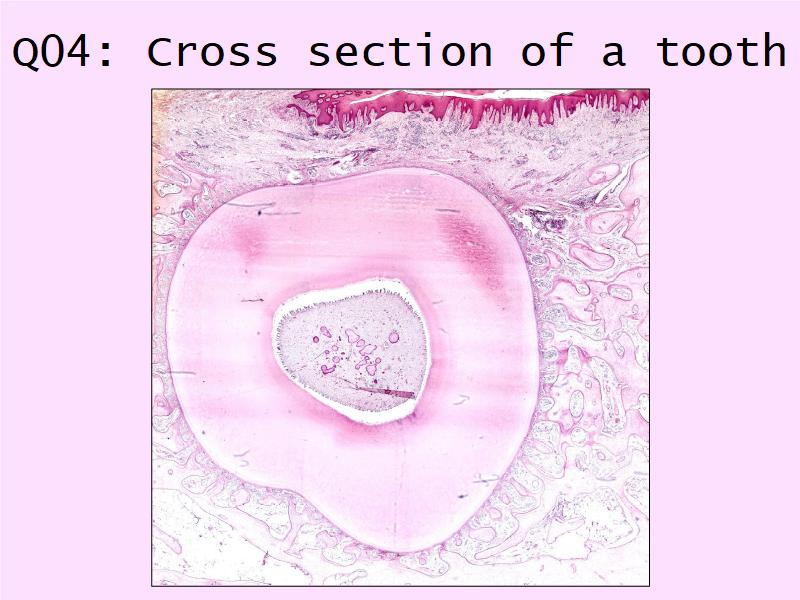

Q01: Terminology

On the next slide, a set of 16 terms will be listed. For each term, mark YES if you know or recognise the term, NO if you don't know the term.Yes = I know or recognise the term

No = I have no idea at all

Q01: Yes or No

|

1. Lumen 2. Low Density Lipoprotein 3. Endothelium 4. Intima 5. Extracellular matrix 6. Monocyte 7. Macrophage 8. Apoptosis |

9. Necrosis 10. Hypertension 11. Arterial wall 12. Smoking 13. Diabetes 14. Smooth muscle cell 15. Plaque 16. Thrombus |

Q01: Yes or No

|

1. Lumen 2. Low Density Lipoprotein 3. Endothelium 4. Intima 5. Extracellular matrix 6. Monocyte 7. Macrophage 8. Apoptosis |

9. Necrosis 10. Hypertension 11. Arterial wall 12. Smoking 13. Diabetes 14. Smooth muscle cell 15. Plaque 16. Thrombus |

9 of 16 = histology

7 of 16 = commonly occuring

Will we ever need to look at slides?

The practical supplies the visual side of the "theoretical" component, and should not be seen as 2 separate topics that should be studied as 2 "subjects".The slides should be used to expand on your lecture.

Histology forms the basis for many clinical situations. Lacking the histology, will mean that you will struggle mastering other fields.